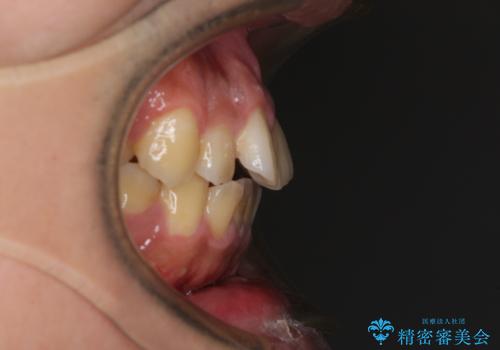

- 高校時代に行った抜歯矯正が後戻りをしたとのことで来院された患者様です。

再矯正であることから、目立ちにくい装置を希望されたため、インビザラインにて矯正治療を行うこととしました。

下顎骨が左側に変位しているため、正中が合わないことは予想できましたが、歯列が整った後も咬み合わせが安定せず、咬み合わせを落ち着かせるために1年以上の期間を要しました。